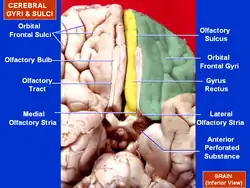

Human brain bottom view. Orbital gyri shown in green. | |

The inferior or orbital surface of the frontal lobe is concave, and rests on the orbital plate of the frontal bone. It is divided into four orbital gyri by a well-marked H-shaped orbital sulcus. These are named, from their position, the medial, anterior, lateral, and posterior, orbital gyri. The medial orbital gyrus presents a well-marked antero-posterior sulcus, the olfactory sulcus, for the olfactory tract; the portion medial to this is named the straight gyrus, and is continuous with the superior frontal gyrus on the medial surface.